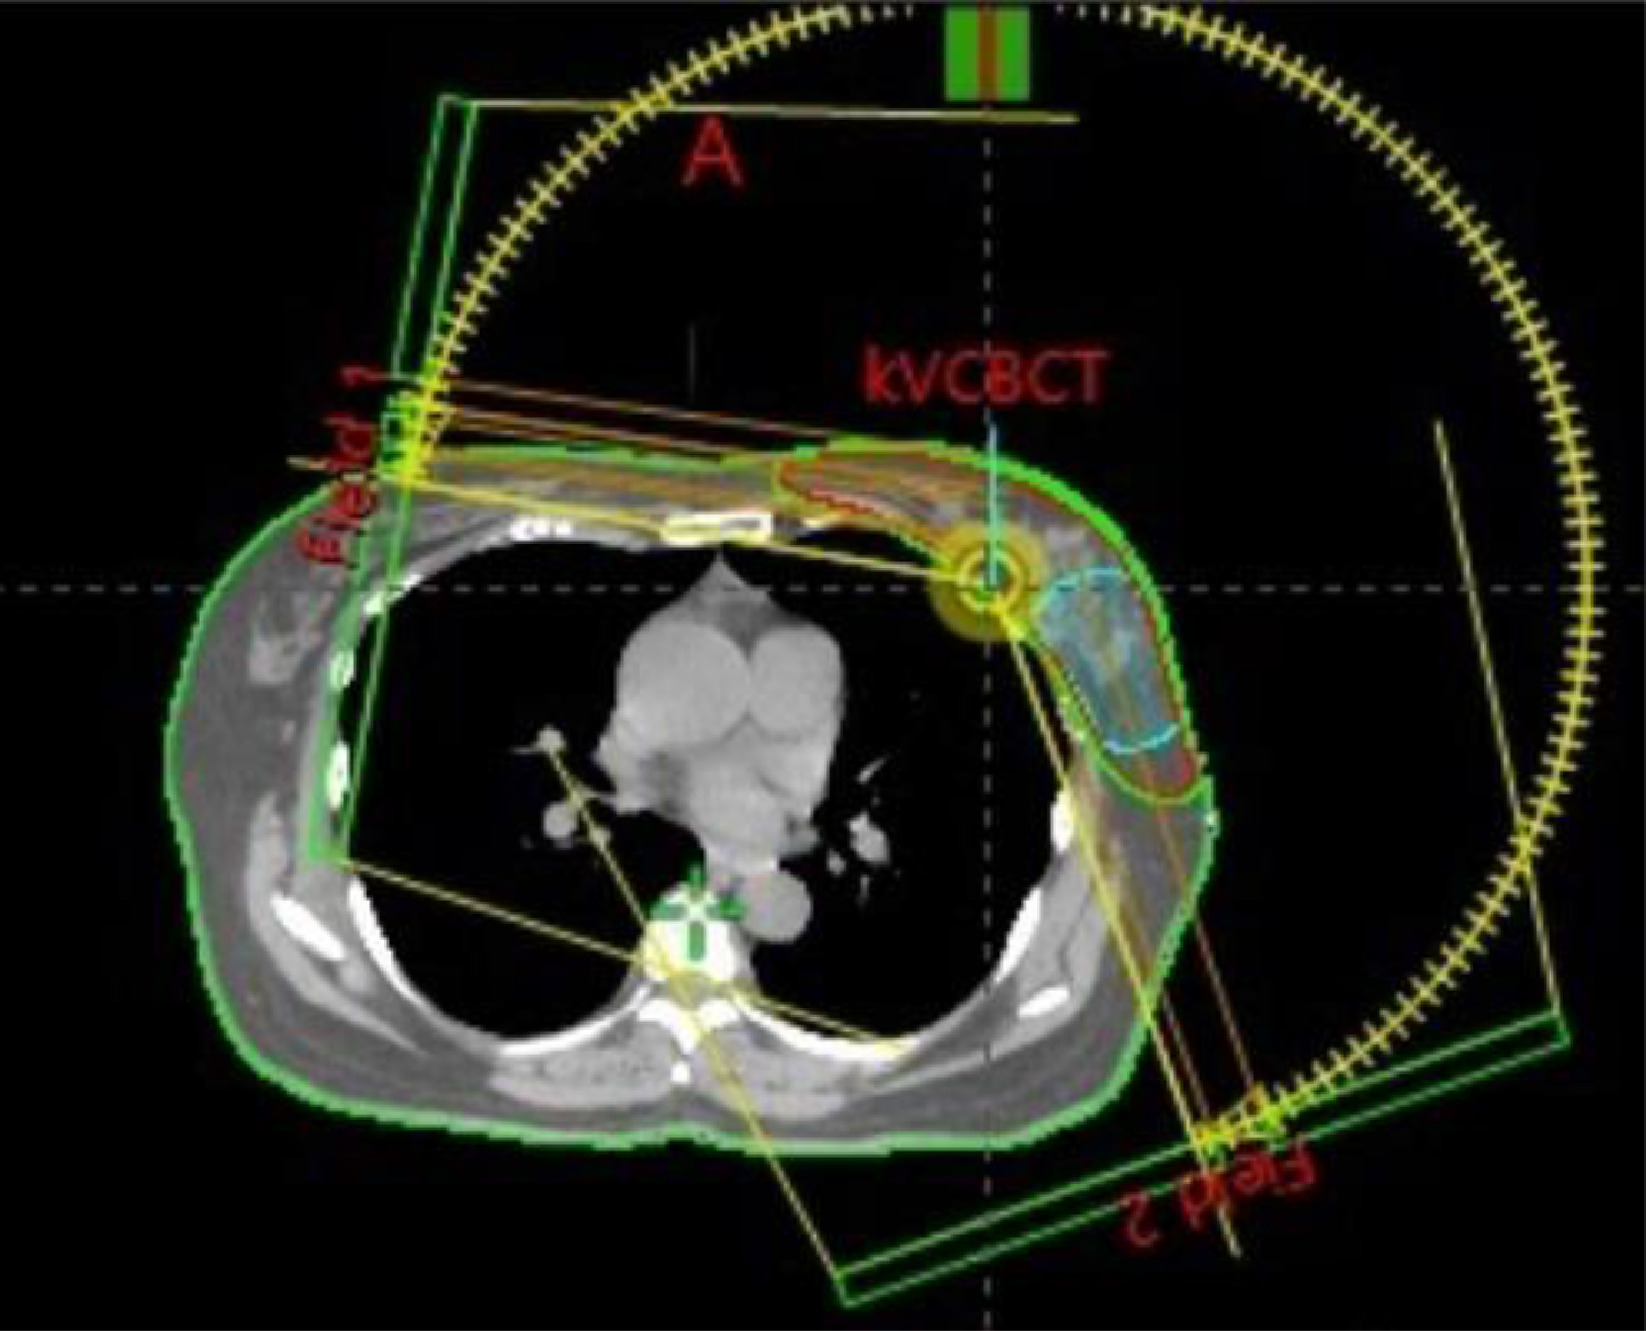

VMAT is a type of radiation therapy that uses advanced technology to treat cancer. Unlike traditional radiation therapy, which delivers radiation from a single angle, VMAT rotates around the patient in a 360-degree arc. This approach allows for precise targeting of the tumor, adjusting the intensity of the radiation beam as it moves, and delivering the optimal dose directly to the cancer cells.

• During a VMAT session, the patient lies still on a treatment table. The machine, known as a linear accelerator, rotates around the patient, delivering radiation in a continuous arc. The intensity and shape of the radiation beam are constantly adjusted to focus on the tumor from multiple angles.

• VMAT's ability to change the radiation intensity and shape in real-time allows for a higher dose to be delivered to the tumor while protecting nearby healthy tissue. This precision reduces side effects and often shortens the overall treatment time compared to traditional methods.